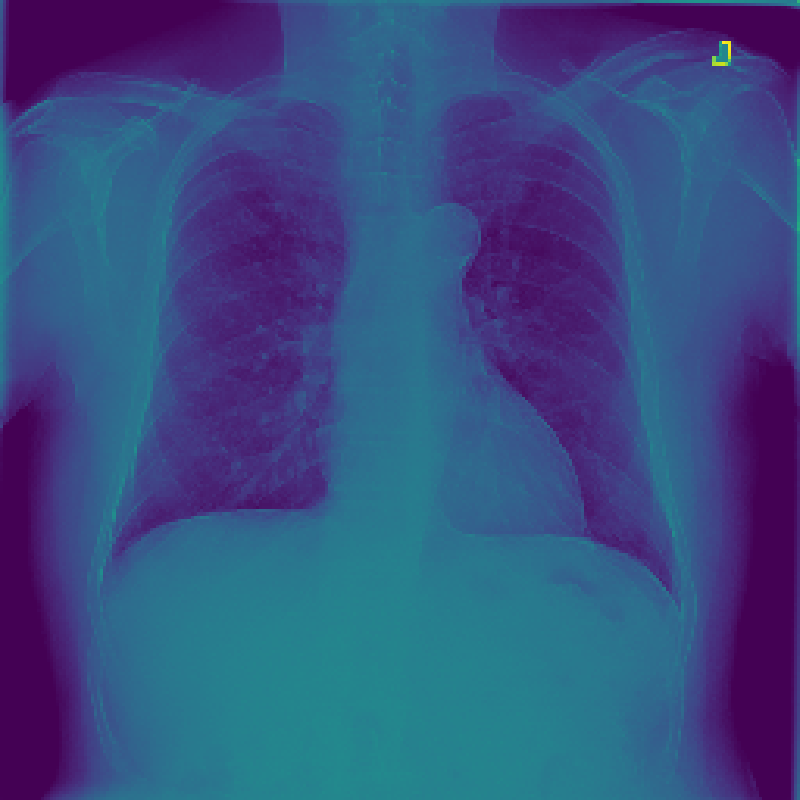

Figure 3: The feature map visualization of the GMSM and QCM modules. (a) Original image; (b) f1subscript𝑓1f_{1}italic_f start_POSTSUBSCRIPT 1 end_POSTSUBSCRIPT in Eq. 1; (c) f2subscript𝑓2f_{2}italic_f start_POSTSUBSCRIPT 2 end_POSTSUBSCRIPT in Eq. 1; (d) f3subscript𝑓3f_{3}italic_f start_POSTSUBSCRIPT 3 end_POSTSUBSCRIPT in Eq. 1; (e) Output of GMSM y𝑦yitalic_y; (f) Output of QCM; (g) Residual between y𝑦yitalic_y and QCM output.

3.2 Visualization of Feature Maps

In this section, we visualize the feature maps of the GMSM and QCM modules, as shown in Figure 3. From Figures 3 to 3, we observe that, during GMSM’s downsampling process, the earlier layers effectively capture the skeletal and organ contours in the X-ray image, while the later layers extract more abstract features. This observation suggests that GMSM progressively extracts key information in a coarse-to-fine manner. As shown in Figure 3, the output from the QCM module closely resembles the feature map of y𝑦yitalic_y in Figure 3. Additionally, the residual map in Figure 3 appears generally darker, indicating the QCM module’s effectiveness in compensating for quantization loss.